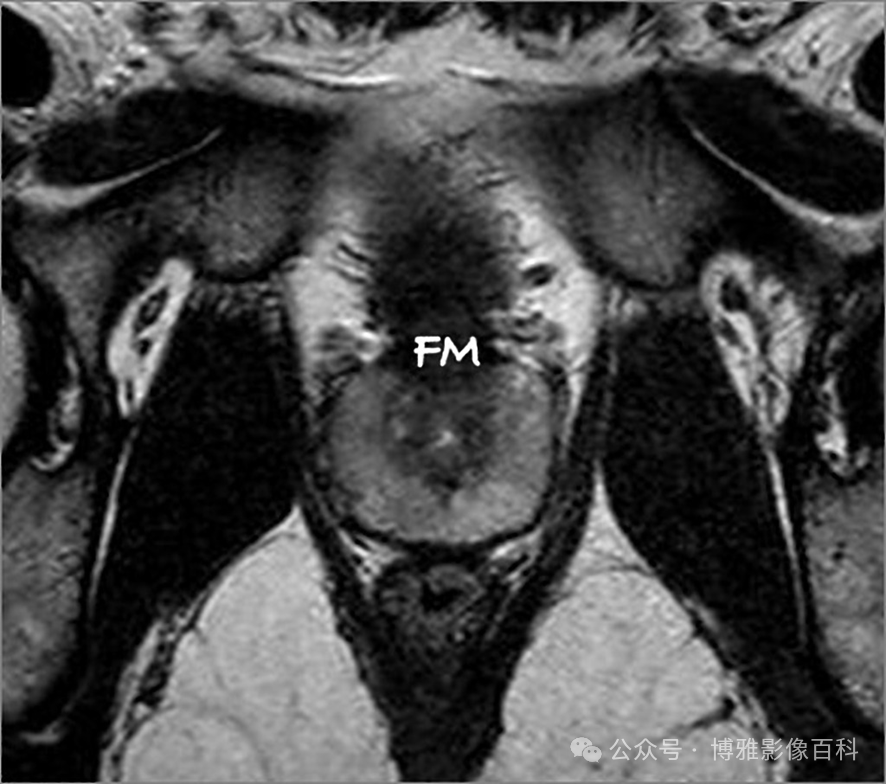

MR 解剖学

前列腺良性增生患者的轴向T2 图像,其他方面正常。外周带是一薄层均匀的高信号,边界清晰连续性的低信号包膜。移行带通常表现为不均匀中等信号,病灶被边界清楚的BPH良性前列腺增生结节所取代。精囊具有均匀T2高信号。未见淋巴结肿大。